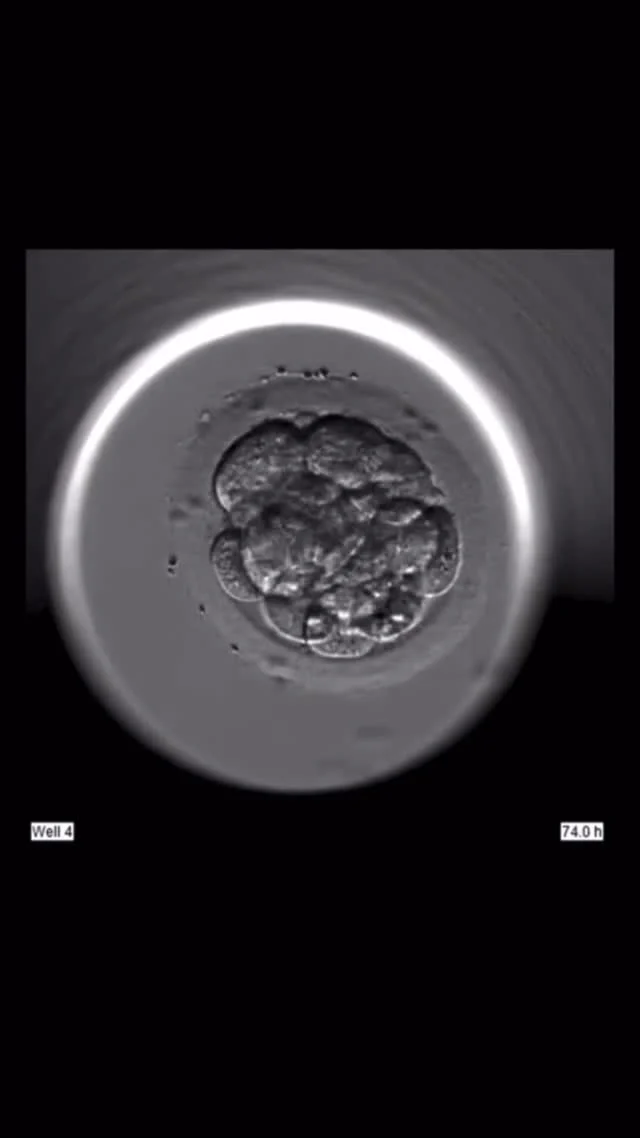

тоциста при эко

Бластоциста при эко 104 фото